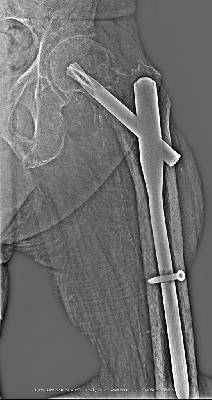

Описание рентгенограммы левого тазобедренного сустава в прямой передне-задней проекции: шейка левого бедра срослась. Контуры малого вертела нечеткие. Щель сустава практически отсутствует. Металлоконструкция PFNA компании Sysntes (Швейцария) стабильна. Костная плотность значительно снижена, пятнистый остеопороз.

Диагноз: Сросшийся базальный перелом шейки левого бедра, состояние после металлоостеосинтеза конструкцией PFNA. Тяжелый остеопороз.

Конструкция PFNA - proximal femor nail antirotation - проксимальный бедренный гвоздь с предотвращением его ротации в кости